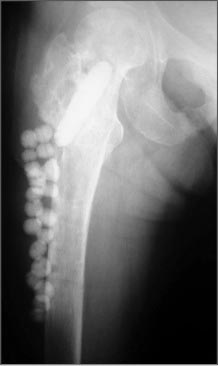

Re: Остеомиелит бедра в условиях МОС

Вертельные переломы хорошо срастаются, но допущенная небольшая флекcия изменила вектор динамического винта и сыграла против скольжения. С момента фиксации прошло достаточное время, и перелом должен срастаться хотя бы частично! Это подтверждается позицией DHS, который, несмотря на сломанные винты, не изменил позицию! Ложный сустав в этой области характерен более драматической картиной, но для уточнения можно сделать КТ!

А что такое современное промывание (Irrigation&Debridment) говорили не раз, желательно в операционной, под общим обезболиванием, адекватно! Если инфекция с гнойным процессом, тогда временно бусы с цементом и вакуум! Во время промывки можно удалить металл и дефект кости заполнить бусами! Сделать стресс тест: отсутствие подвижности доказывает частичное сращение и бусы можно оставить. При наличии подвижности необходимо фиксировать, хотя бы наружным фиксатором - в шейку и в диафиз! При более интенсивном вовлечении в гнойный процесс процедуру можно повторить. Перекись и антисептики токсичны и плохо влияют на заживление!

Здесь пример лечения антибиотическими бусами и форма для бус!